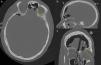

La presencia de aire dentro de la cavidad intracraneal es una entidad rara que se conoce con el nombre de neumoencéfalo y en la mayoría de los casos no presenta repercusión clínica salvo cuando ocasiona un aumento de la presión intracraneal que puede llegar a producir un deterioro del nivel de conciencia, coma e incluso la muerte.

Presentamos un caso, poco frecuente, de un varón joven sin antecedentes personales de interés que ingresa en una unidad de cuidados intensivos para vigilancia tras un accidente de tráfico con traumatismo craneoencefálico asintomático y con tomografía computarizada craneal de ingreso «sin hallazgos significativos». Durante su estancia en la unidad de cuidados intensivos se aplica presión positiva en la vía aérea con ventilación mecánica no invasiva que genera entrada de aire en la cavidad intracraneal (neumoencéfalo) que condiciona deterioro neurológico importante con necesidad de cirugía urgente.

The presence of air inside intracranial cavity is a rare entity known as pneumocephalus and in most cases doesn¿t present any clinical repercussion except in case of elevated intracranial pressure that can lead to a decreasing level of consciousness, coma and even death.

We present a rare case of a young male, without medical precedents of interest, hospitalized in an intensive care unit for vigilance after a traffic accident with asymptomatic crane encephalic trauma and cranial computerized tomography without meaningful findings. During the intensive care unit stay positive pressure is applied in airway with non-invasive mechanical ventilation that produces air entrance in cranial cavity (pneumocephalus) causing neurological deterioration and necessity of urgent surgery.